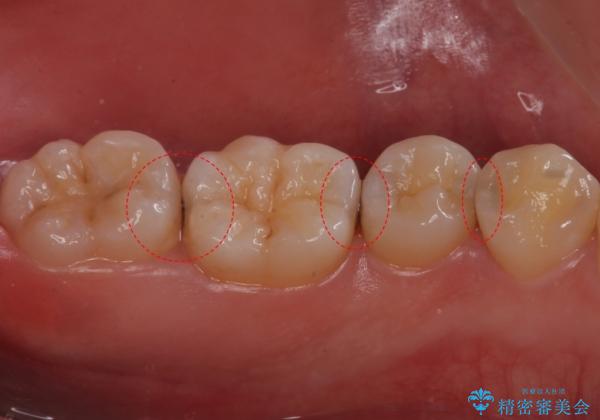

歯と歯の間に虫歯があったため適合の良いセラミックインレーで修復処置をしていきました。

歯と歯の間は虫歯の好発部位となっています。

適合の良いインレーでの修復により再発のリスクを下げることができます。